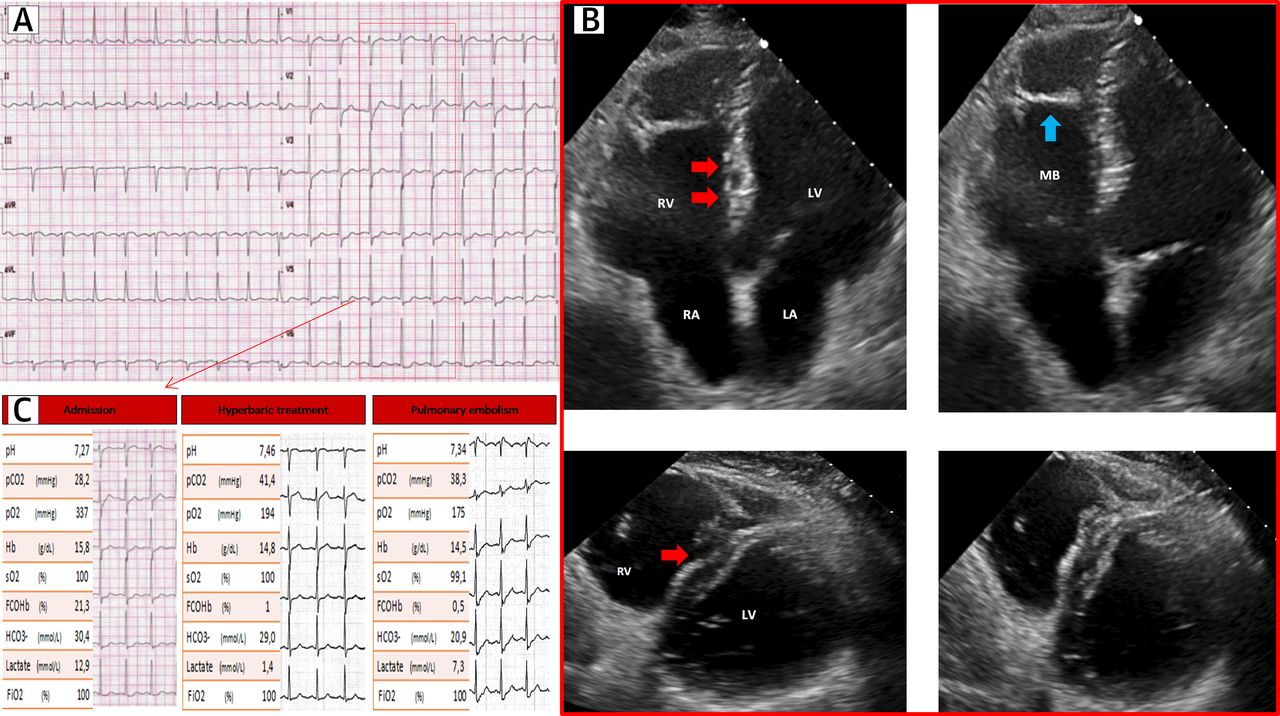

心电图,超声心动图和生化检查结果